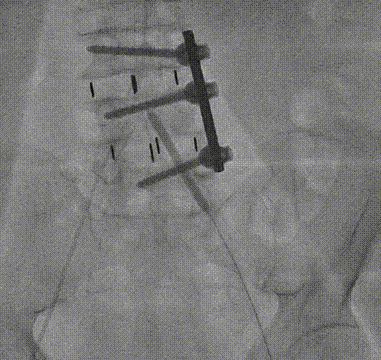

手术过程

入路造影显示左髂总动脉-左股总动脉严重狭窄伴钙化

边打造影剂边缓慢撤20F沛嘉大鞘,发现血管夹层

沿导丝送入10mm×100mm覆膜支架至左髂动脉-股总动脉

复查下肢造影显示右髂总动脉-右股总动脉明显狭窄